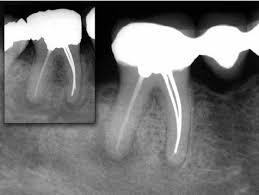

How Dentists Diagnose the Condition

Diagnosis typically involves:

• Clinical examination

• Percussion testing (tapping on the tooth)

• Dental X-rays

X-rays help identify changes in the bone around the root tip, although early inflammation may not always be visible immediately.